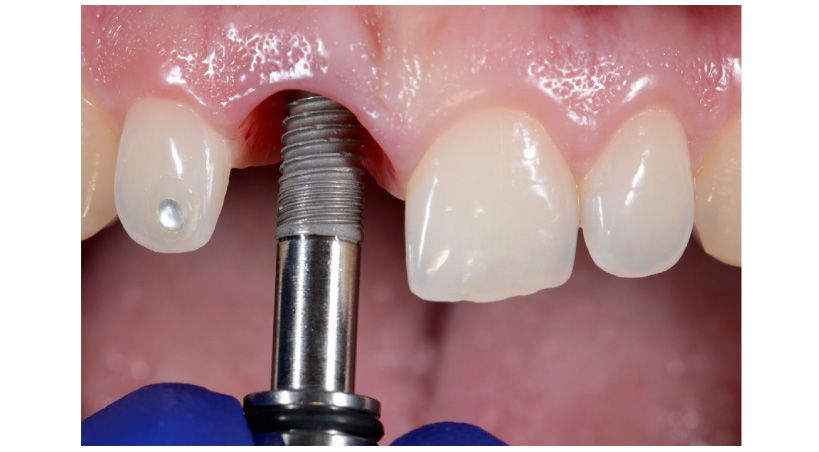

Implantología

Influencia de los factores quirúrgicos y protésicos en la salud o enfermedad periimplantaria

Recomendaciones clínicas de un consenso de expertos de la Sociedad Española de Periodoncia (SEPA)